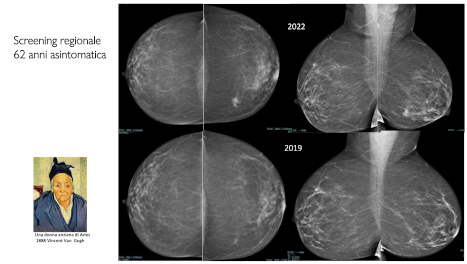

CASI ECOGRAFICI SETTIMANALICaso clinico a cura della d.ssa Teresa Abbattista

Caso clinico a cura della d.ssa Teresa Abbattista